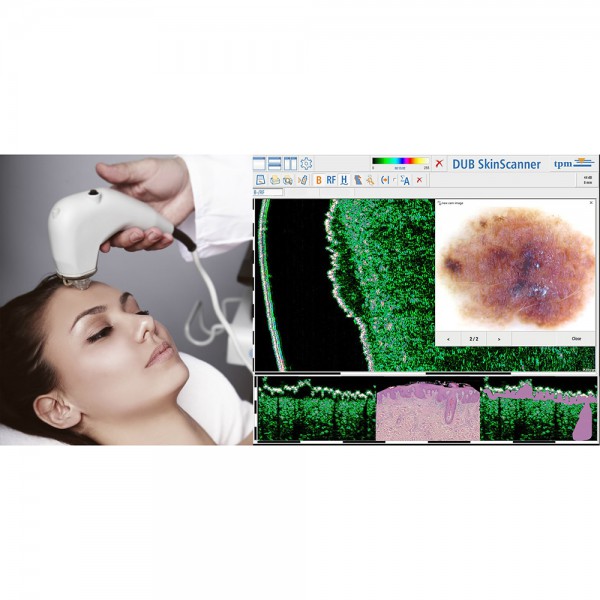

-Υπέρηχος Υψηλής Συχνότητας (HFUS) και Ιστολογία

Εφαρμογές δερματολογίας

-Κύριες εφαρμογές

-Κύριες παθολογικές διεργασίες